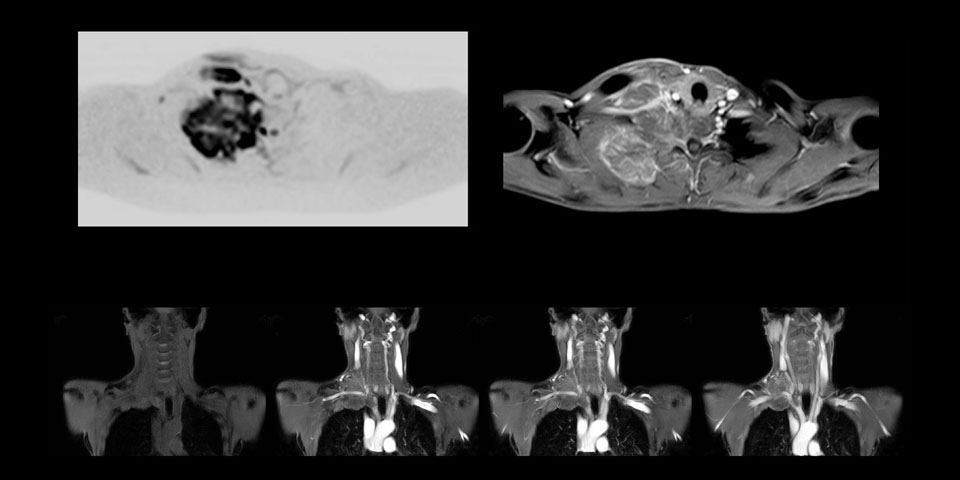

MRI of Pancoast tumor

Although the area between the neck and the top of the lung is one of the most difficult areas for MRI, Prodiva 1.5T images show good quality in this 56-year-old male with Pancoast tumor on the right. mDIXON TFE images shows excellent fat suppression in the neck area and the DWI shows almost no distortion.

Prodiva MRI pancoast tumor DWI, Seirei Mikatahara

Prodiva MRI pancoast tumor mDixon, Seirei Mikatahara

Prodiva MRI pancoast tumor dynamic, Seirei Mikatahara